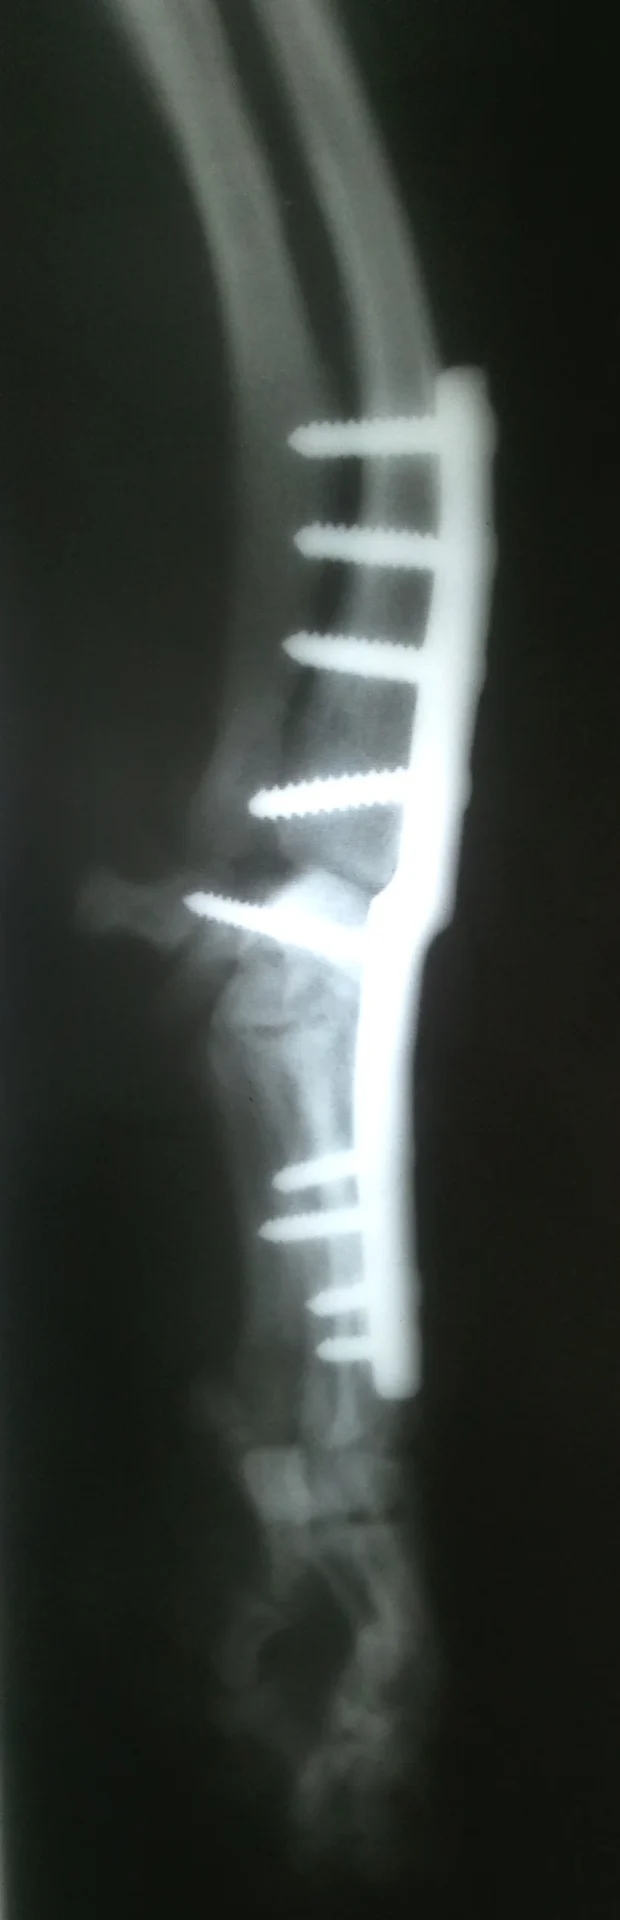

Galería de casos clínicos

Casos clínicos de cirugía (tejidos blandos, traumatología, neurocirugía, artroscopia)